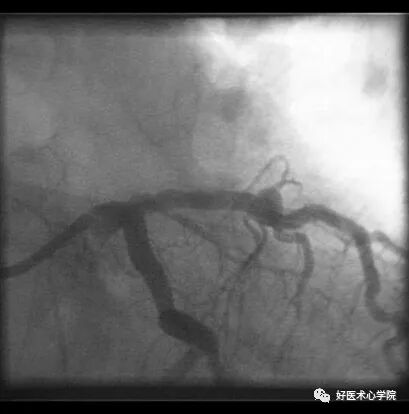

后前位:可以显示左冠大致轮廓;

缺点:左主干、前降支、回旋支分叉处显示不清。

造影导丝是什么珍藏 冠脉造影从流程到诊断,基础必备!_https://www.jmylbn.com_新闻资讯_第47张